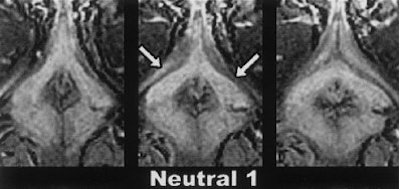

The authors reported the strongest activation at the mesodiencephalic junction, including the ventral tegmental area (VTA), the subparafascicular nuclear, and the medial and ventral thalamus. Increased rCBF was also found in the anterior nucleus of the right thalamus and in the inferior temporal cortex.

Activations are superimposed on the averaged MRI of the volunteers. Activation in the secondary visual cortex (b, BA 18) and the posterior cingulate/precuneus (c, BA 23/31) can be found. Note in sections a-c that the activation in the mesodiencephalic transition zone (mes-di) extends from the rostral midbrain into the ventral parts of the caudal thalamus x = 12 mm left to the intercommissural line. Holstege G, Georgiadis JR, Paans AM, Meiners LC, van der Graaf FH, Reinders AA, "Brain activation during human male ejaculation," J Neurosci 2003 Oct 8:23(27):9185-93. Copyright 2003 by the Society for Neuroscience.

Finally, "remarkably strong rCBF increases were observed in the cerebellum," they said. "These findings corroborate the recent notion that the cerebellum plays an important role in emotional processing."